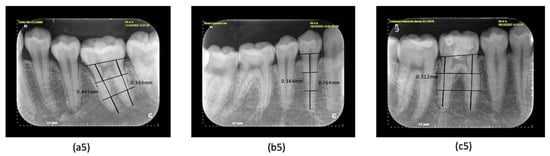

| Periapical Radiograph Examination | Irregularity of alveolar crest | 16 (40%) | 24 (60%) | 40 |

| Periodontal ligament width (PDL) | 16 (40%) | 24 (60%) | 40 |